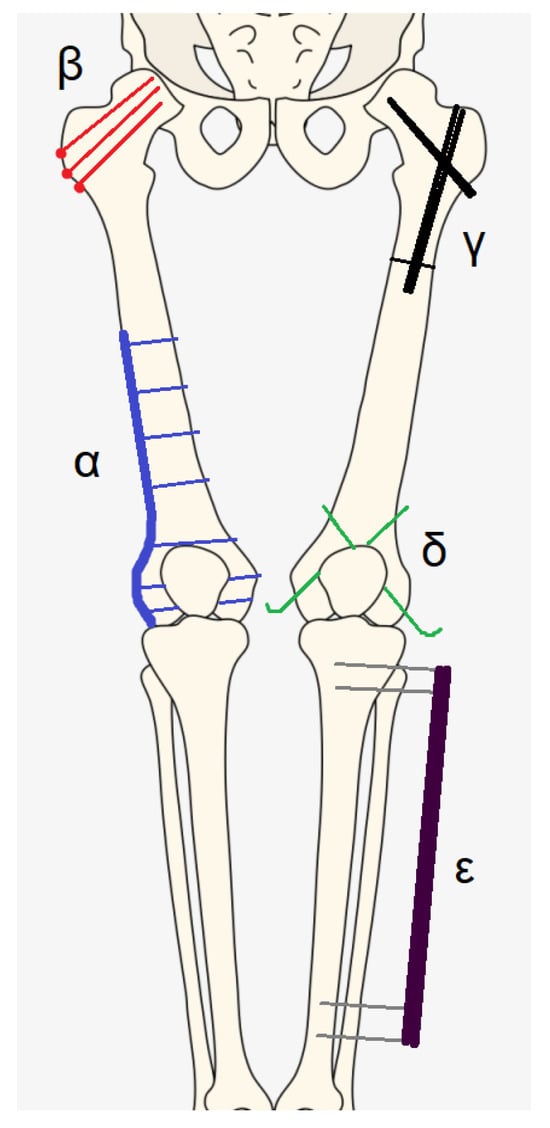

- α: plate and screws;

- β: screws;

- γ: nail;

- δ: K-wires;

- ε: external fixator.

| HARDWARE | Corresponding Letter of the Greek Alphabet |

|---|---|

| Plate and screws | Alfa (α) |

| Screws | Beta (β) |

| Nail | Gamma (γ) |

| K wires | Delta (δ) |

| External fixator | Epsilon (ε) |